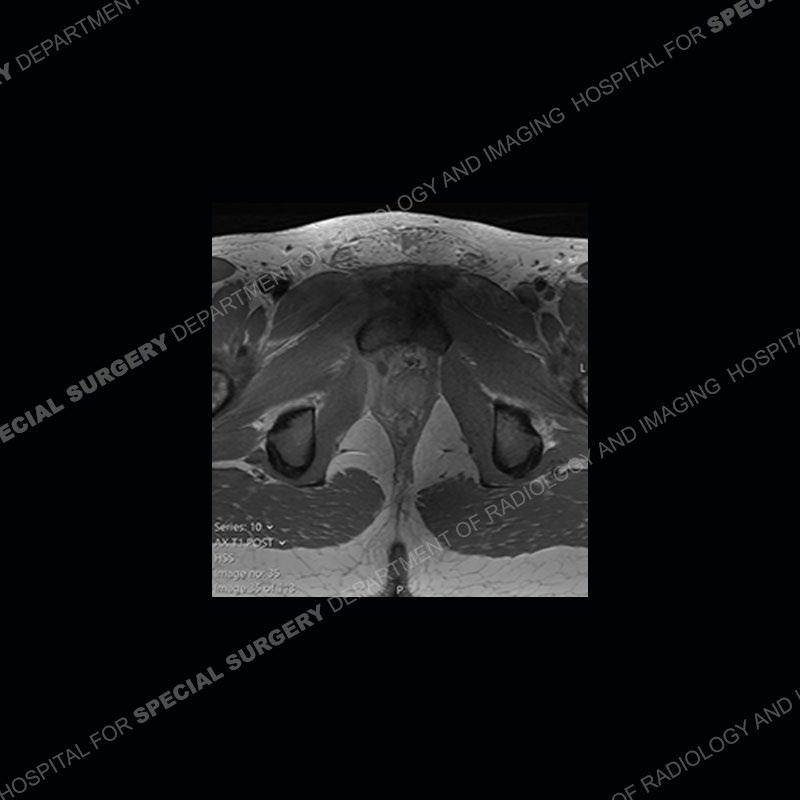

Radiographs did not demonstrate any clear abnormality. The MRI shows markedly abnormal signal of the right superior pubic ramus and abnormal signal/”mass” extending into the adjacent soft tissue. The inferior articular surface of the ramus showed what was thought to be bony destruction. CT examination shows a destructive process of the right superior pubic ramus.

Subsequent MRI in a very short time interval shows markedly increased abnormality of the ramus and increased edema and “mass” of the soft tissue. Post contrast imaging shows multiple, rim enhancing collections of the soft tissue and similar albeit less conspicuous enhancing collection of the ramus.